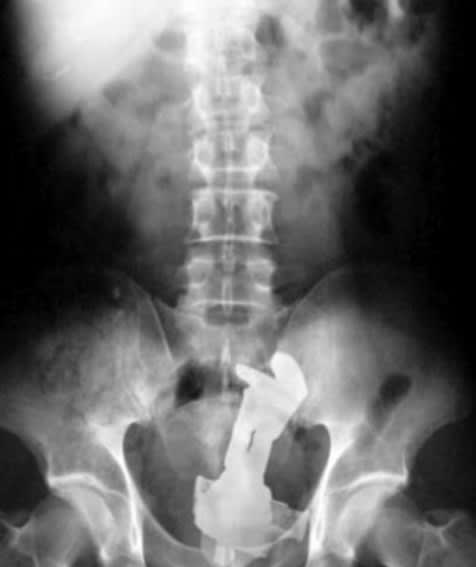

Petit jeu : le premier qui a trouvé l'ensemble des éléments coincés , a gagné 😊

Img 0276 dqheev - Eugenol

Img 0277 ys5kfq - Eugenol

Img 0278 g6kug0 - Eugenol

Img 0279 pw9nhc - Eugenol

Img 0280 uek1bu - Eugenol

Img 0281 snk6hv - Eugenol

Img 0282 q9rlwp - Eugenol

la K7 c'est trop 80's la barbie aussi, non?